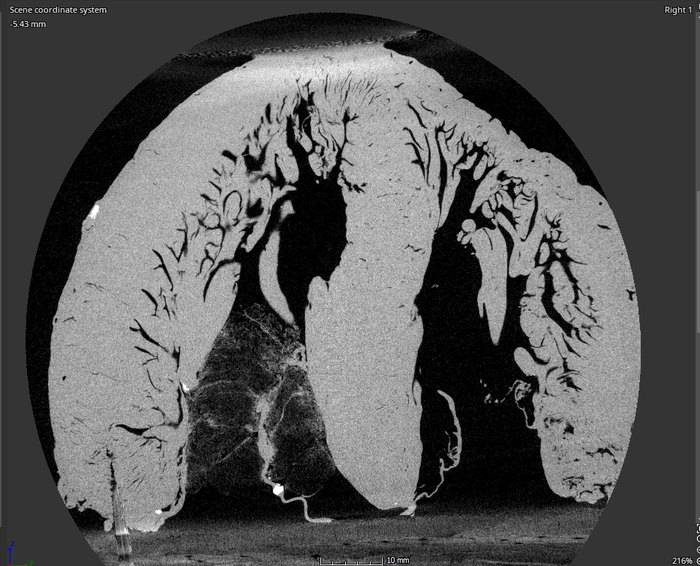

Southwest Research Institute and The University of Texas at San Antonio are collaborat-ing to create a computer model of the tubular structures in the human heart as part of a larger effort to develop a new, potentially life-saving heart surgery. These structures, called the trabeculae carneae, are poorly understood and most models of the heart ig-nore them. (Credit: SwRI)

Within the human heart are numerous small muscle bundles called the trabeculae carneae. Despite their significance to the heart’s anatomy, their function is not well understood, and most models of the heart ignore them.

“Capturing the intricate structures of the trabeculae carneae requires something more powerful than an MRI or standard CT scanners,” Bartels said. “We’ll utilize a micro-focus X-ray CT scanner here at SwRI to create images of explanted human hearts.”

The images of the heart’s intricate inner structures will help Han to create a realistic anatomical model of the trabeculae carneae, building on a previous model he developed for the left ventricle.